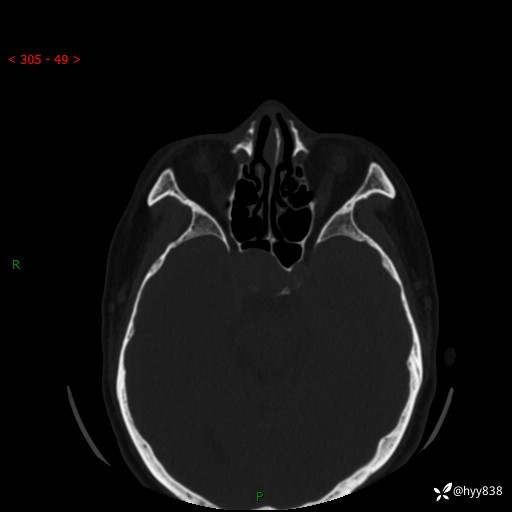

蝶鞍CT平扫